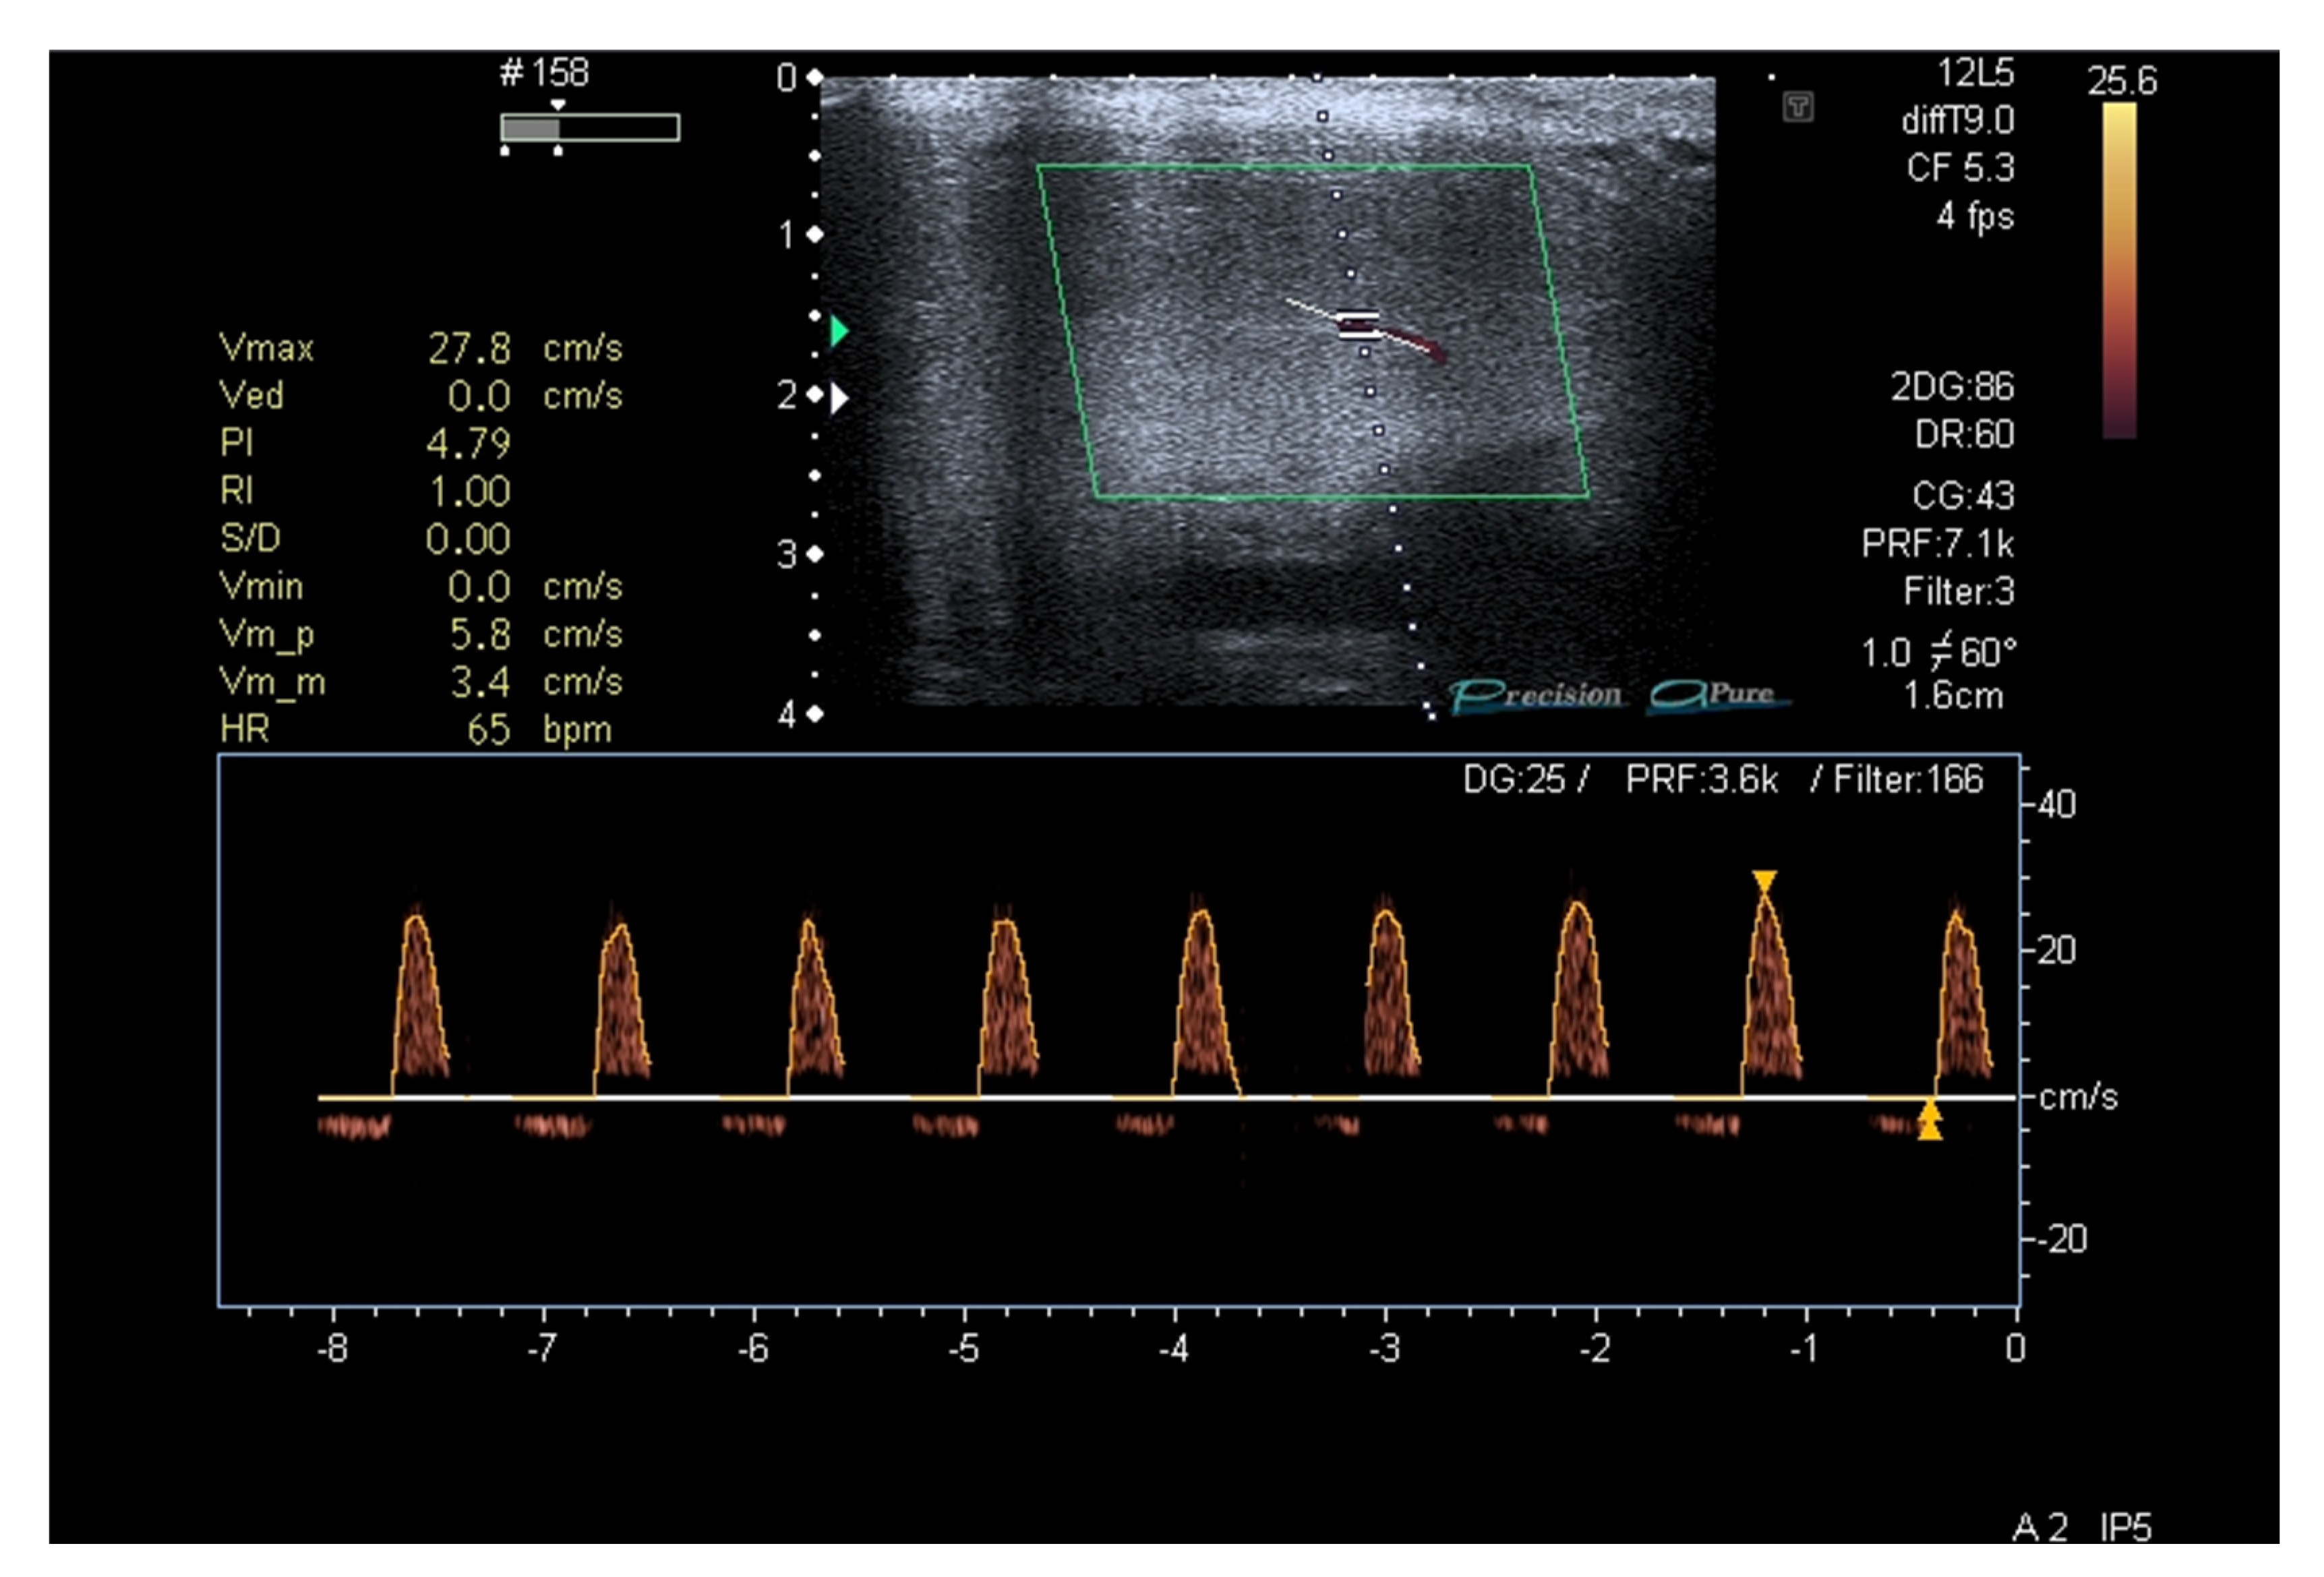

- Aversa, A.; Crafa, A.; Alessandra Greco, E.; Chiefari, E.; Brunetti, A.; La Vignera, S. The Penile Duplex Ultrasound: How and when to perform it? Andrology 2021, 9, 1457–1466. [Google Scholar] [CrossRef]